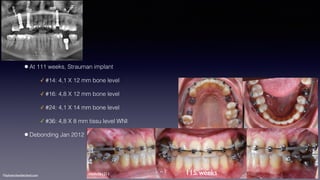

•At 111 weeks, Strauman implant

✓ #14: 4,1 X 12 mm bone level

✓ #16: 4,8 X 12 mm bone level

✓ #24: 4,1 X 14 mm bone level

✓ #36: 4,8 X 8 mm tissu level WNI

•Debonding Jan 2012